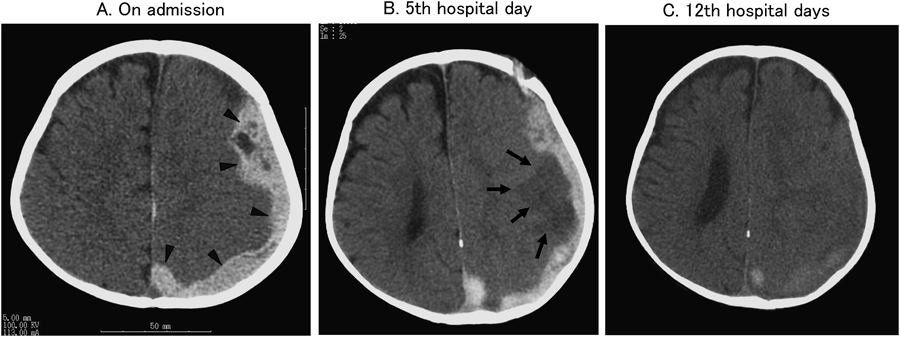

入院の10日前に3回の嘔吐が出現したが神経学的異常所見なく,Domperidone投与で速やかに改善した.入院前日の朝から活気低下,夜間に38.5°Cの発熱を呈し,嘔吐,機嫌不良も出現した.頭部CT検査(Fig. 2(A))で左大脳半球表面に広範な硬膜下血腫を認めた.体表面に明らかな痣や外傷はなく,栄養状態は良好,皮膚の清潔も保たれ虐待は否定された.同時に機械弁開放/閉鎖音の減弱を認め,人工弁透視検査(Fig. 1)を施行したところ一葉が閉鎖位で固定していた.心臓超音波検査では,大動脈弁通過血流速度2.8 m/sと,発症前の2.1~2.5 m/sより若干加速していたが,心機能は良好で心不全も来していなかった.PT-INRは5.08と顕著に延長していたため,FFP(90 mL:10 mL/kg),Vitamin K2(4 mg)を投与しPT-INRは8時間後に2.01に低下,さらにFFP(90 mL:10 mL/kg)を追加し24時間後に1.25まで低下した.入院2日目の頭部CTでは血腫の増大は見られなかった.この間,APTT 70 sec.を目標に未分化Heparinを持続投与した.入院5日目,頭部CTで血腫は吸収,縮小したが左中大脳動脈領域に梗塞像が出現した(Fig. 2(B)).右握力は僅かに低下していたが他の麻痺や痙攣は認めなかった.入院12日目の頭部CT(Fig. 2(C))で血腫はほぼ吸収されていることを確認し,PT-INR2.0を目標にWarfarin内服を再開した(Fig. 3).人工機械弁の一葉完全開放,一葉閉鎖位固定の状況には変化がなかったため待機的再手術の方針とし,ICH発症4か月後に再弁置換術を施行した.ICHの再発は認めず,右握力は発症前と同等に改善し,他の麻痺,痙攣を含む神経学的後遺症も認めていない.

Pediatric Cardiology and Cardiac Surgery 32(1): 9-18 (2016)

Fig. 2 Head CT

A: Subdural hematoma (). Mild midline shift and disappearance of the sulcus were observed. B: Although subdural hematoma diminished, a new cerebral infarction was found (). C: The subdural hematoma was almost completely absorbed.